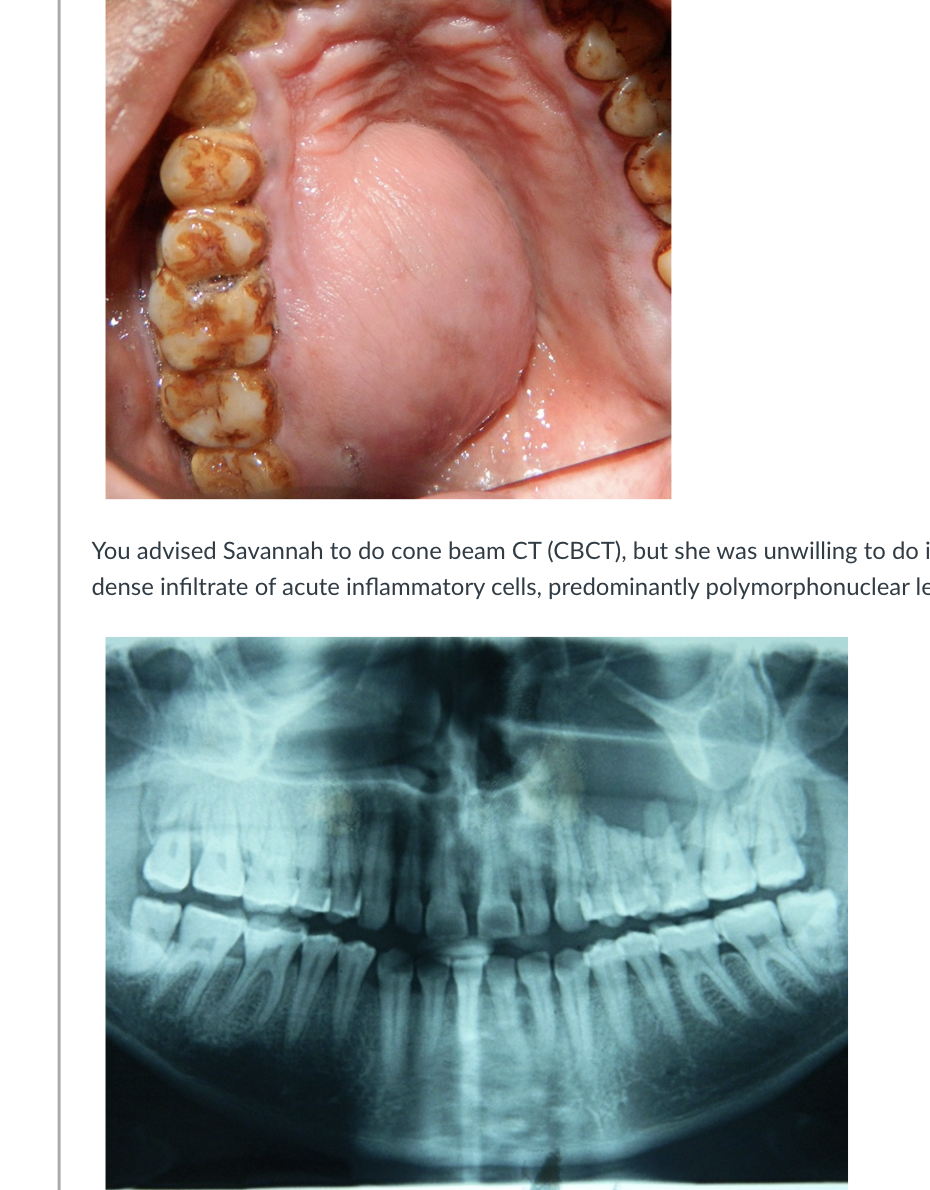

Savannah Bridge, a 32-year-old patient, came to your dental clinic with a primary complaint of mild pain and the presence of pus discharge in her upper left jaw. During the clinical examination, a noticeable swelling was observed on the palate, extending from teeth 25 to 28, crossing the midline (please refer to the accompanying image). Ms. Bridge reported a history of visiting multiple private dental clinics over the past 6 months, where she received antibiotics and pain relievers for the same persistent swelling. Her medical history did not reveal any significant health issues. Tooth 26 exhibited caries on the mesio-proximal surface and showed no signs of vitality. Surprisingly, the adjacent teeth (24, 25, 27, and 28) remained vital. Upon palpation, the swelling felt soft and fluctuant. No swelling or draining sinus tract was detected in the buccal vestibule, and there were no palpable lymph nodes. Ms. Bridge’s oral hygiene was notably poor, with significant staining and calculus buildup.

You advised Savannah to do cone beam CT (CBCT), but she was unwilling to do it due to financial constraints. Hence, orthopantamograph was taken (please see the image below). Along with the OPG, intraoral periapical radiograph, maxillary occlusal radiograph and routine laboratory investigations were done. Radiographic examination revealed a large unilocular radiolucency with well-defined radiopaque border. Routine laboratory investigations were within normal limits. Fine needle aspiration revealed opaque, brown-coloured fluid, consisting dense infiltrate of acute inflammatory cells, predominantly polymorphonuclear leukocytes. Few isolated epithelial cells were seen, which were normal in size, shape, and appearance. Cytological picture was suggestive of an acute inflammatory lesion.

Radiographic findings: Large unilocular radiolucency with a well-defined radiopaque border, typical of a radicular cyst.

Aspiration results: Opaque, brown-colored fluid with inflammatory cells supports an inflamed cyst.

Patient history: Chronic swelling unresolved by antibiotics suggests a cyst rather than an acute infection.

Conclusion: Radiographic, aspirate, and clinical evidence align with the diagnosis of an inflamed radicular cyst.